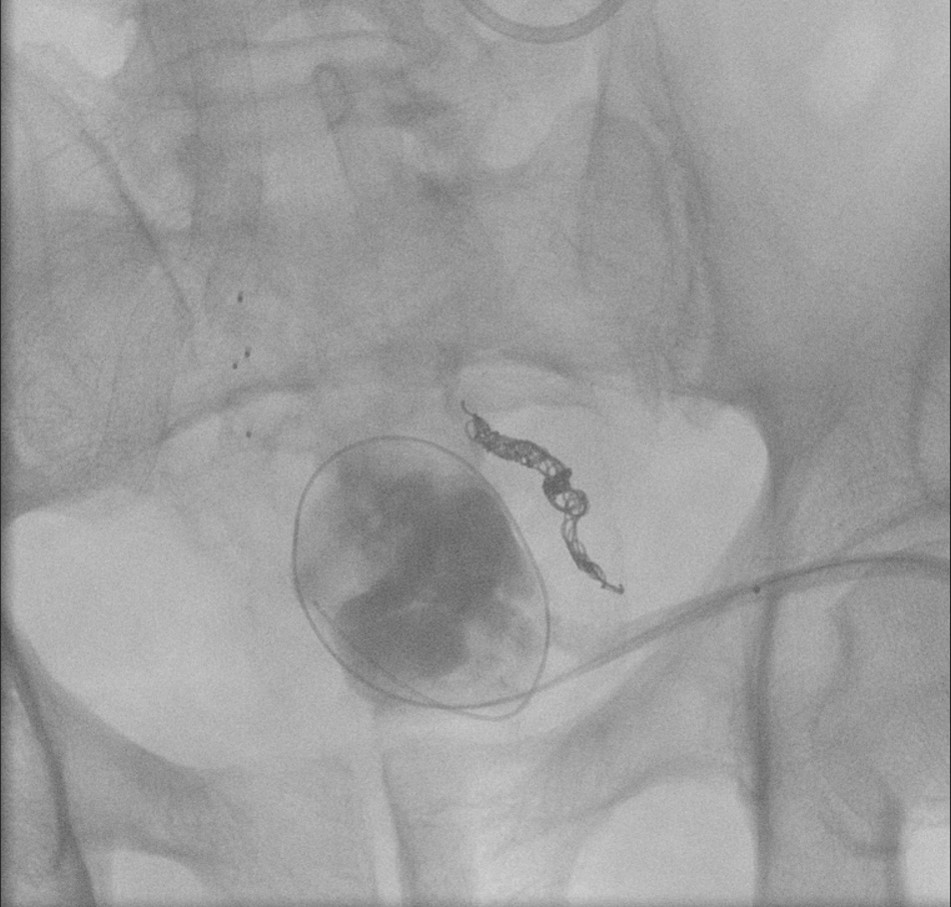

- The gynecologist will begin injecting contrast material into the uterus. Obtain images periodically throughout the procedure (usually at the direction of the gynecologist). The images should include the uterine cavity filled with contrast material, bilateral fallopian tubes filled with contrast material, and spillage and dispersion of contrast material into the peritoneal cavity (image 1) (image 2) (image 3) (image 4) (image 5).